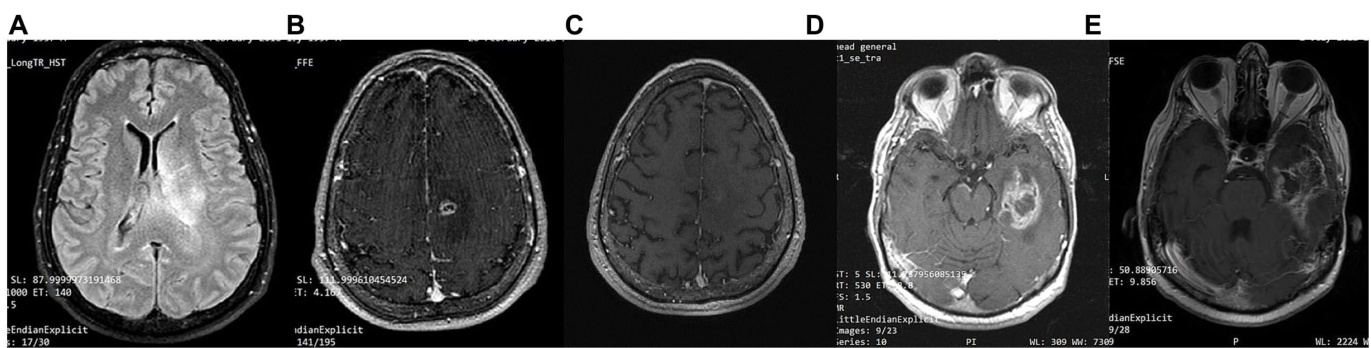

A 63-year-old man was diagnosed in February 2018 with GBM following a first epileptic seizure. The patient experienced an episode of focal seizures involving the right upper and lower limb. On neurological examination, a mild right-sided hemi pares is was noted. Brain MRI revealed a large heterogeneous ly enhancing tumor in the left parietal lobe with a central nodule and surrounding vasogenic oedema, extending through the corpus callosum to the contra lateral side (Figure 7). An EEG demonstrated paroxysmal activity consisting of intermittent sharp theta waves on the left fronto central region and the patient was put on le vet i race tam. Stereo tactic brain biopsy and his to pathological examination confirmed IDH1-negative GBM (Figure 4). The patient was considered inoperable due to the extent of the tumor, which infiltrated the corpus callosum and extended across the midline. The patient received radiotherapy (30 sessions, 60 Gy in total) along with chemotherapy (temozolomide) and corticosteroids (dex amet has one per os). A 3:1 ketogenic diet was initiated in April 2018 just before radiotherapy (Table 3). After radiation therapy, corticosteroids were gradually withdrawn and the patient was maintained on a treatment regimen of $250\mathrm{mg}$ temozolomide in total per day for 5 days every 4 weeks (until July 2019), alongside ketogenic diet therapy. The diet was well-tolerated, and the patient achieved and maintained ketosis (ketonemia $3{-}4\mathrm{mmol/L}$ ) and lower blood glucose levels $(70{-}85\mathrm{mg/dL})$ throughout the follow-up period. Brain MRI was performed every 3 months showing no tumor progression and less surrounding vasogenic oedema, while the enhancing nodule in the left semioval center was decreasing with minor enhancement (Figure 7).

2018年2月,一名63岁男性首次癫痫发作后被诊断为胶质母细胞瘤(GBM)。患者出现累及右上肢和右下肢的局灶性癫痫发作。神经系统检查发现轻度右侧偏瘫。脑部MRI显示左顶叶存在一个大型异质性强化肿瘤,中央有结节并伴有周围血管源性水肿,肿瘤通过胼胝体延伸至对侧 (图7)。脑电图显示左额中央区出现阵发性间歇性尖θ波活动,患者开始服用左乙拉西坦。立体定向脑活检及组织病理学检查确诊为IDH1阴性胶质母细胞瘤 (图4)。由于肿瘤范围广泛,已浸润胼胝体并跨越中线,患者被判定为无法手术。患者接受了放疗(30次,总剂量60Gy)联合化疗(替莫唑胺)及皮质类固醇治疗(口服地塞米松)。2018年4月放疗前开始采用3:1生酮饮食 (表3)。放疗结束后逐渐停用皮质类固醇,并维持每4周服用5天(每日总量$250\mathrm{mg}$)替莫唑胺的治疗方案(持续至2019年7月),同时配合生酮饮食疗法。患者对饮食方案耐受良好,在整个随访期间保持酮症状态(血酮$3{-}4\mathrm{mmol/L}$)及较低血糖水平$(70{-}85\mathrm{mg/dL})$。每3个月进行的脑部MRI显示肿瘤无进展且周围血管源性水肿减轻,同时左半卵圆中心强化结节逐渐缩小且强化程度减弱 (图7)。

However, 32 months after diagnosis, the patient suffered a GBM relapse (Figure 7). While continuing the ketogenic diet, he underwent surgical resection and was put on second line chemotherapy with bevacizumab $(5{-}7\mathrm{mg/kg})$ and irinotecan $\mathrm{120~mg/m^{2}},$ ) until his death in September 2021 (43 months post-diagnosis).

然而,确诊32个月后,患者出现胶质母细胞瘤复发 (图 7)。在坚持生酮饮食的同时,他接受了手术切除,并开始使用贝伐珠单抗 $(5{-}7\mathrm{mg/kg})$ 和伊立替康 $\mathrm{120~mg/m^{2}}$ 进行二线化疗,直至2021年9月去世 (确诊后43个月)。

FIGURE 7 Patient 4: (A) brain MRI on diagnosis (T2/FLAIR) (B) brain MRI on diagnosis (T1 with contrast) (C) 24-month follow-up brain MRI (T1 with contrast) (D) 32-month follow up brain MRI. GBM relapse (T1 with contrast) (E) 41-month follow up brain MRI (T1 with contrast).

图 7: 患者4: (A) 确诊时脑部MRI (T2/FLAIR) (B) 确诊时脑部MRI (增强T1) (C) 24个月随访脑部MRI (增强T1) (D) 32个月随访脑部MRI。胶质母细胞瘤复发 (增强T1) (E) 41个月随访脑部MRI (增强T1)